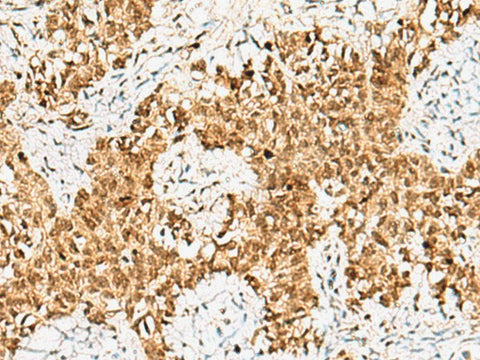

CRCP Polyclonal Antibody Reactivity Human

Applications IHC

IHC 1:50-1:200